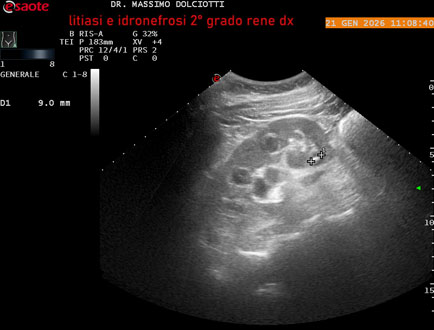

Data inserimento: 22/01/2026

Ecografia del: 21/01/2025

Strumento: Esaote MyLab Eight

Sonda: Convex Multifrequenza 1-8 MHz

Età Paziente: M 27 anni

Motivazione dell'esame: dolore al fianco destro da 3 mesi.

Commento all'esame: le immagini ed il video documentano il rene destro in sede, con ecostruttura disomogenea per evidenza, alla pelvi renale, di immagine iperecogena delle dimensioni di 16,2 mm, con cono d'ombra posteriore, da ricondurre a litiasi ed una formazione simile, di minore entità, al polo inferiore, delle dimensioni di 6,8 mm. Rene dx con diametro longitudinale di 122 mm (v.n. 90-120 mm) x 63 mm e parenchima renale dello spessore di 15 mm (v.n. > 13 mm). Rene dx con idronefrosi di 2° grado.

Conclusioni: litiasi e idronefrosi di 2° grado al rene destro (lithiasis and second-degree hydronephrosis of the right kidney).

In collaborazione: Dr.ssa Marica Manfredi - Ancona, Dr. Ilir Qose - Ancona

Presentazione: Dr. Massimo Dolciotti - Ancona

Elaborazione digitale: Andrea Dini - Ancona